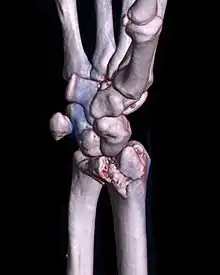

A palmar Barton's fracture of the right wrist, as shown on a 3D-rendered CT scan